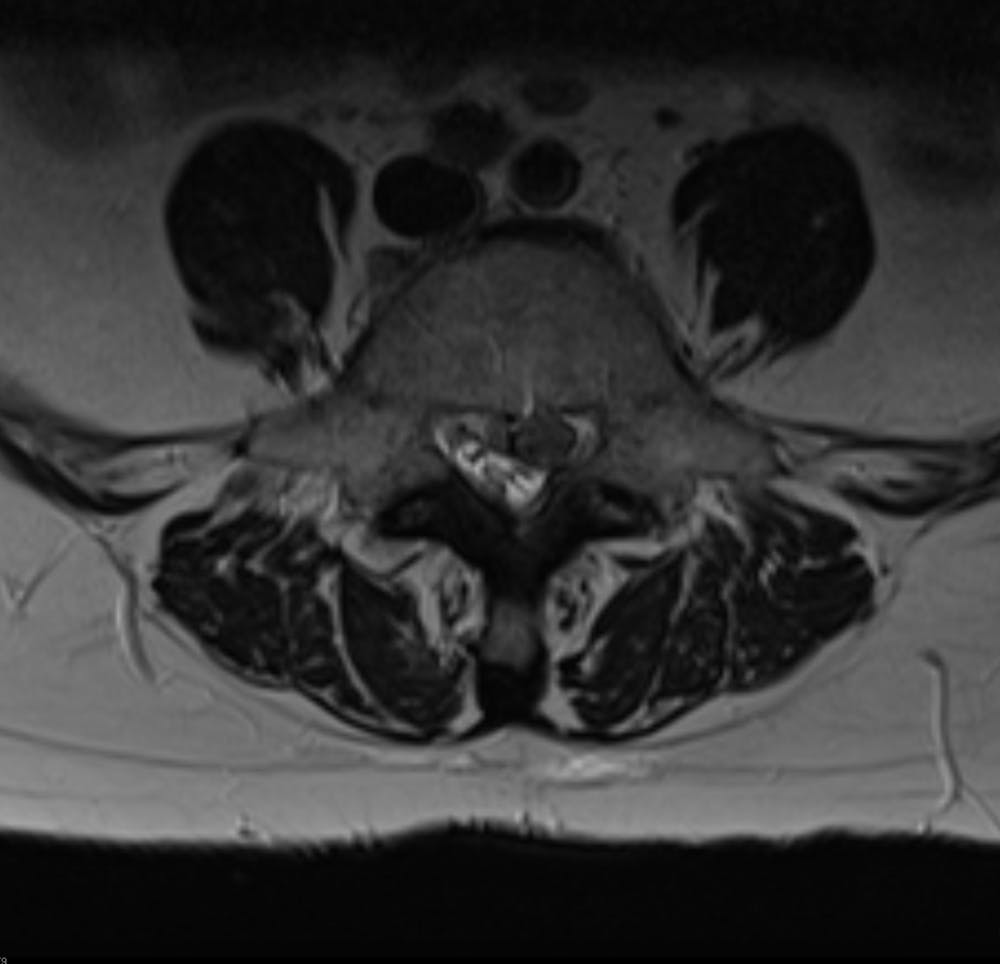

Ruptures or tears in the annulus fibrosus in a disc leads to moderate-to-severe lower back pain. This device was developed ease suffering, improve surgical outcomes, and prevent a recurrence of herniation, and avoid the need for an aggressive removal of the remaining disc nucleus.

Intrinsic Therapeutics developed the Barricaid device to close large defects in the annulus, the outer part of a spinal disc.

- Barricaid is used after discectomy, which is a surgery to remove lumbar herniated disc material that may be pressing on a nerve root or the spinal cord, causing pain.

- The procedure has proven to prevent recurrent disc herniation.